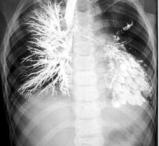

Бронхография — основной, окончательно подтверждающий диагноз метод. Он не только констатирует наличие бронхоэктазов, но и позволяет уточнить их локализацию, форму и размеры. Бронхография проводится после предварительной санации бронхиального дерева с помощью муколитических и отхаркивающих средств (а иногда даже бронхоскопического лаважа бронхов) и купирования воспалительного процесса. На бронхограмме в пораженном отделе отмечается расширение бронхов различной формы, их сближение и отсутствие заполнения контрастным веществом ветвей, располагающихся дистальнее бронхоэктазов. Бронхографически различают бронхоэктазы цилиндрические, мешотчатые, веретенообразные, смешанные, а также единичные, множественные, ограниченные и распространенные. С помощью бронхографии можно в определенной степени сделать заключение о дренажной функции бронхов — по способности их эвакуировать рентгеноконтрастное вещество йодлипол. Время эвакуации при бронхоэктазах резко увеличено, причем степень увеличения зависит от формы, величины, локализации бронхоэктазов и выраженности бронхоспастического синдрома.